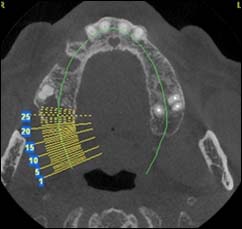

EXAMENS TOMOGRAPHIES VOLUMIQUES TYPE SCANNER OU CÔNE BEAM :

Dernière technologie à notre disposition, cette technique permet de voir en 3 dimensions des images de votre bouche et de mettre en évidence des pathologies ou des anomalies que les autres techniques ne permettent pas d’objectiver.

Reconstruction coronale